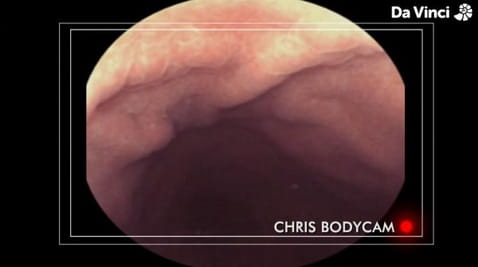

4. Komory mózgowe i połknięta kamera

5. Podróż z ust do żołądka

10. Widok z wnętrza jelit